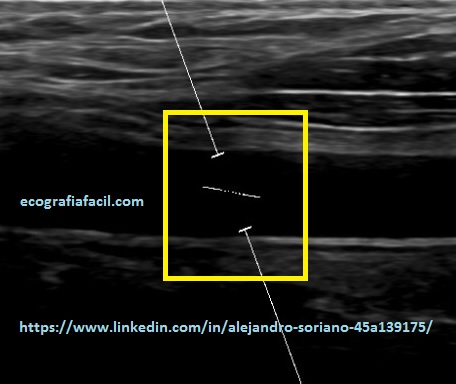

Como vemos en las tres imágenes con distintas angulaciones obtendremos un espectro bastante decente pero no en todos los casos obtendremos datos suficientemente fiables.

En la imagen 10 tenemos un ángulo inferior a 60º pero la línea de la angulación no es paralela.

En la imagen 11 hemos conseguido poner la línea paralela pero a cambio de una angulación superior a 60º; por tanto, tendremos que “jugar” con la angulación del vaso y la del propio Doppler para tener un ángulo inferior a 60º y que quede la línea paralela a la pared del vaso como tenemos en la imagen 12. Esto nos permitirá tener la tranquilidad de que los datos obtenidos serán más fiables.